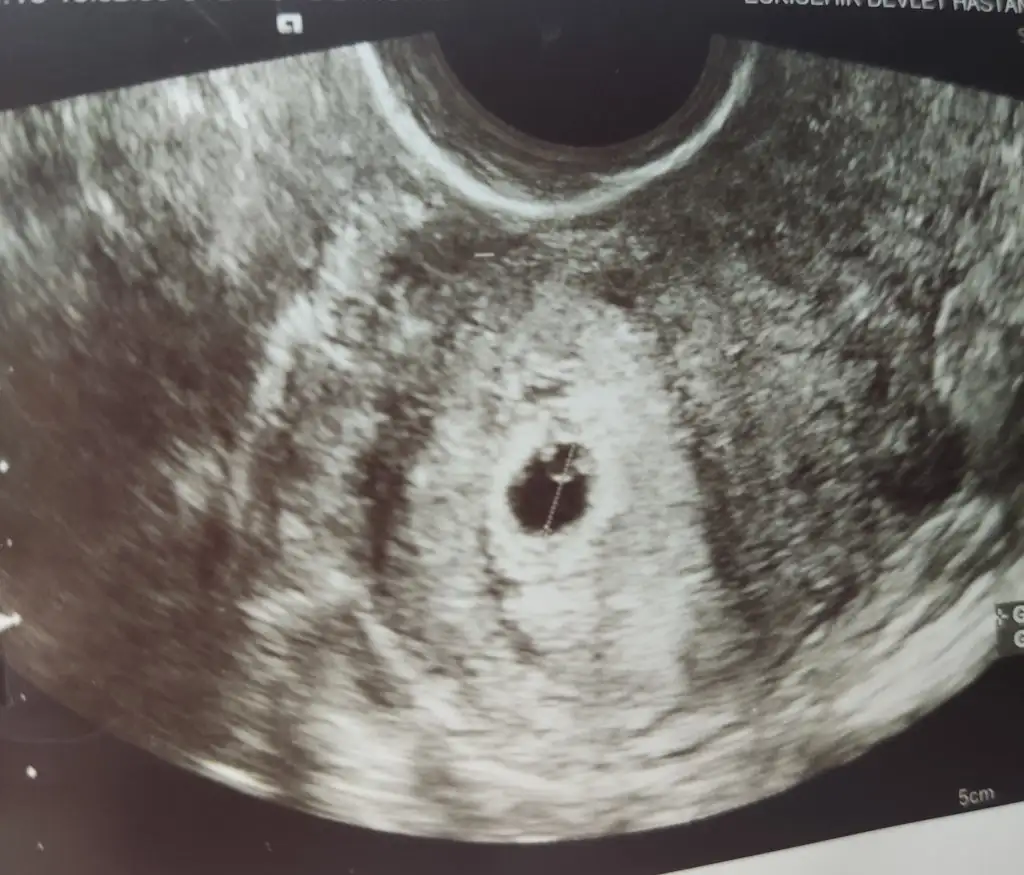

Bende tam bugün bu konuda post açmıştııımmmkeseyi ve yolk sacı gördüüüük bugün hemdeee Allah'ım herkese nasiiiip etsiiin